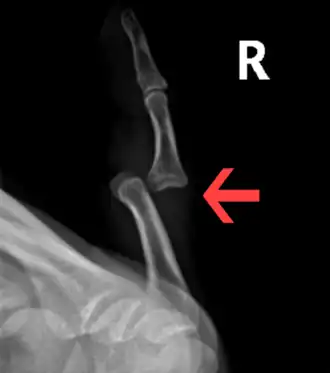

-

Dislocation of the left index finger -

Radiograph of right fifth phalanx bone dislocation -

Radiograph of left index finger dislocation

Radiograph of right fifth phalanx dislocation resulting from bicycle accident -

Right fifth phalanx dislocation resulting from bicycle accident